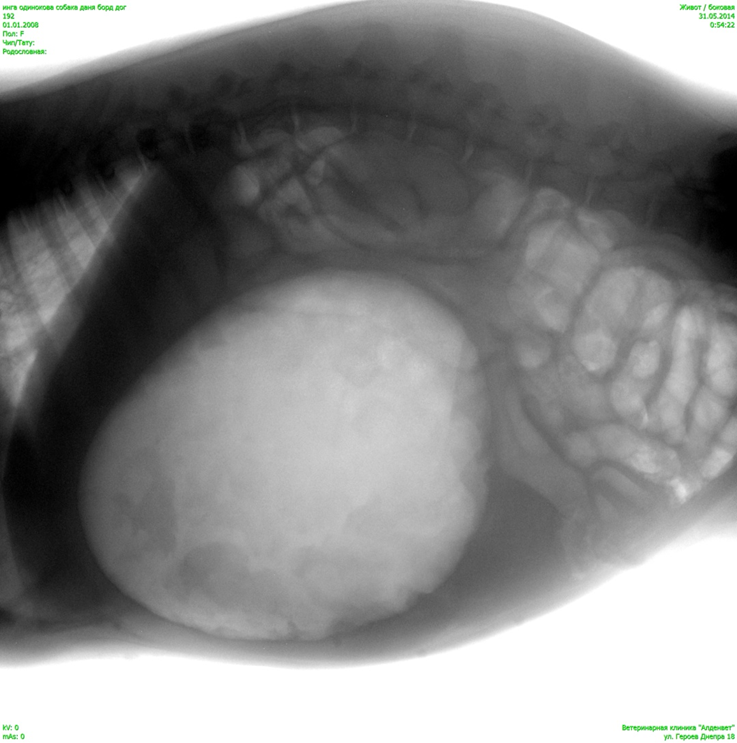

Оберіть рентгенівське зображення відповідно діагнозу.

View this question

Яка викладка (проекція) зображена на знімку:

рентген